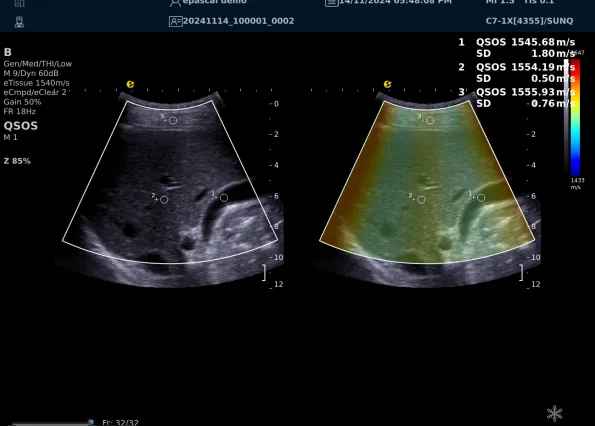

以上为应用声速定量成像技术检查肝脏的超声图像,图中在取样框内选择了三个测量区域,得出了各区域内的组织声速值以及声速衰减系数等结果。